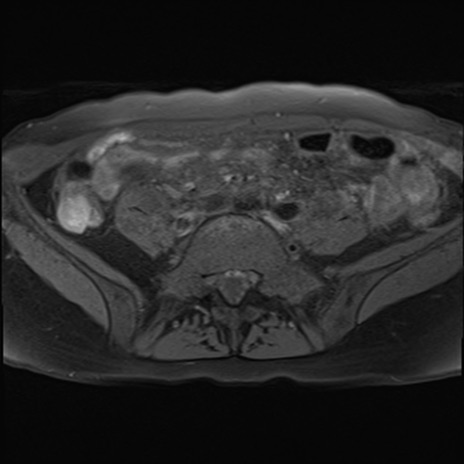

症例39 脂肪抑制T1WI(横断像)

MRI(4日後)

T1WI(横断像)